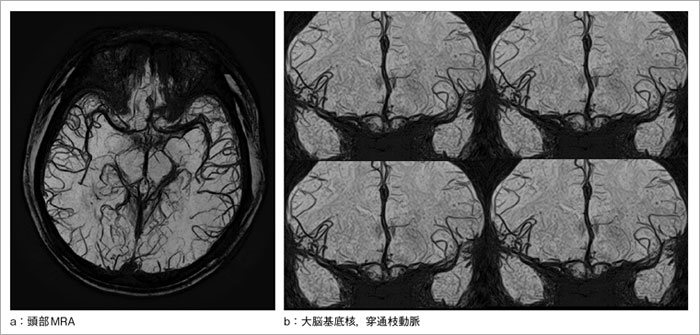

FSBB法は,3D収集の高分解能T2強調像をベースにしたMRAである。従来のT2強調像で見られる位相情報の付加によるマジックアングルの影響がないため,元画像の信頼性が向上する1)。また,ベースがT2*強調像なため,微小出血巣や静脈血管の描出が可能となる。この元画像のベーシックな描出能に,ディフュージョンで用いられているMPG(motion probing gradient)パルスを加えて血流信号のde-phase効果を促進させ,さらなる血管描出能の向上を図った点が最大の特長である(図1)。

この結果,1.5T装置となっても,FSBB法を用いることで,脳底動脈穿通枝のような微細な血管を鮮明に描出できるようになった2)。FSBB法は今後,虚血性脳疾患における側副血行路の描出や,動脈吻合術のフォローアップへの適応,また,近年話題となっている血栓溶解療法(t-PA)後の血流評価など,さまざまな臨床応用への期待が高まっている3)

図1 FSBB画像